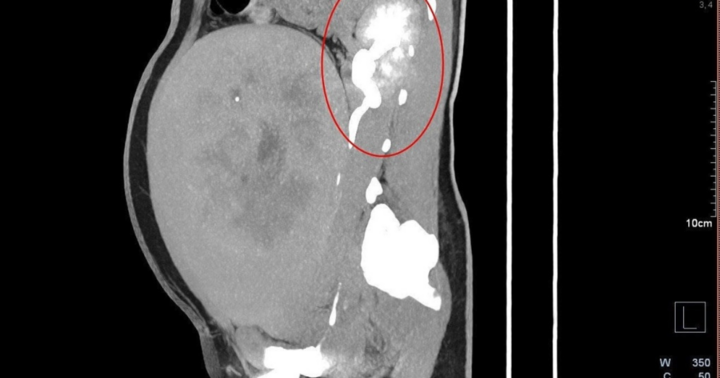

Cách đây vài tháng, khi đi khám sức khỏe định kỳ, chị ngỡ ngàng khi bác sĩ nói chị đã mang thai 18 tuần. Trước đó, khi thấy chu kỳ không đến như bình thường, chị cho rằng bản thân đã mãn kinh nên không đi để ý. Nghe tin chị mang thai tự nhiên ở tuổi 50 mà không hề hay biết, nhiều người xung quanh rất ngạc nhiên.

Để giữ thai, cặp vợ chồng ngoài 50 này đã phải trải qua nhiều khó khăn về sức khỏe, tinh thần, đặc biệt những tuần cuối thai kỳ… nhưng họ đã kiên trì vượt qua. Sau mổ đẻ ngày 19/7, sức khỏe của hai mẹ con ổn định.

Hồi tháng 4, Bệnh viện 354 Hà Nội cũng đỡ đẻ thành công cho người phụ nữ 51 tuổi quê Bắc Kạn, đã có cháu nội. Thai phụ này cảm thấy bất thường trong bụng, cảm giác có "động đậy", đi khám thì phát hiện thai đã ở tuần thứ 22.